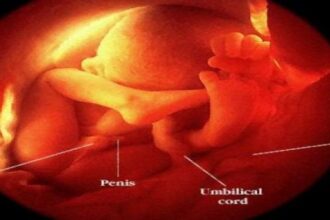

Bebeğin boy uzunluğu 37 cm ve ağırlığı (kilosu) 1000 gramdır. Bu haftada bebek gözlerini rahatlıkla açarak kapatır. Beyin gelişimi hala devam etmektedir ve dışarıdan gelen seslere anne karnında tepki vermektedir. Bebek parmaklarını emmeye başlar ve kendini bu şekilde sakinleştirir ve çene kasları oldukça gelişmiştir. Anne karnındaki bebekte ağlama durumu ortaya çıkar. Bu haftada erken doğan bebeklerde genelde %85 yaşama ihtimali vardır. Doğuma daha henüz 13 hafta varken bu haftada erken doğan bebek zayıf olduğu için vücut ısısının korunması açısından küvez içinde suni solunum yaparak süreci tamamlaması gerekmektedir.